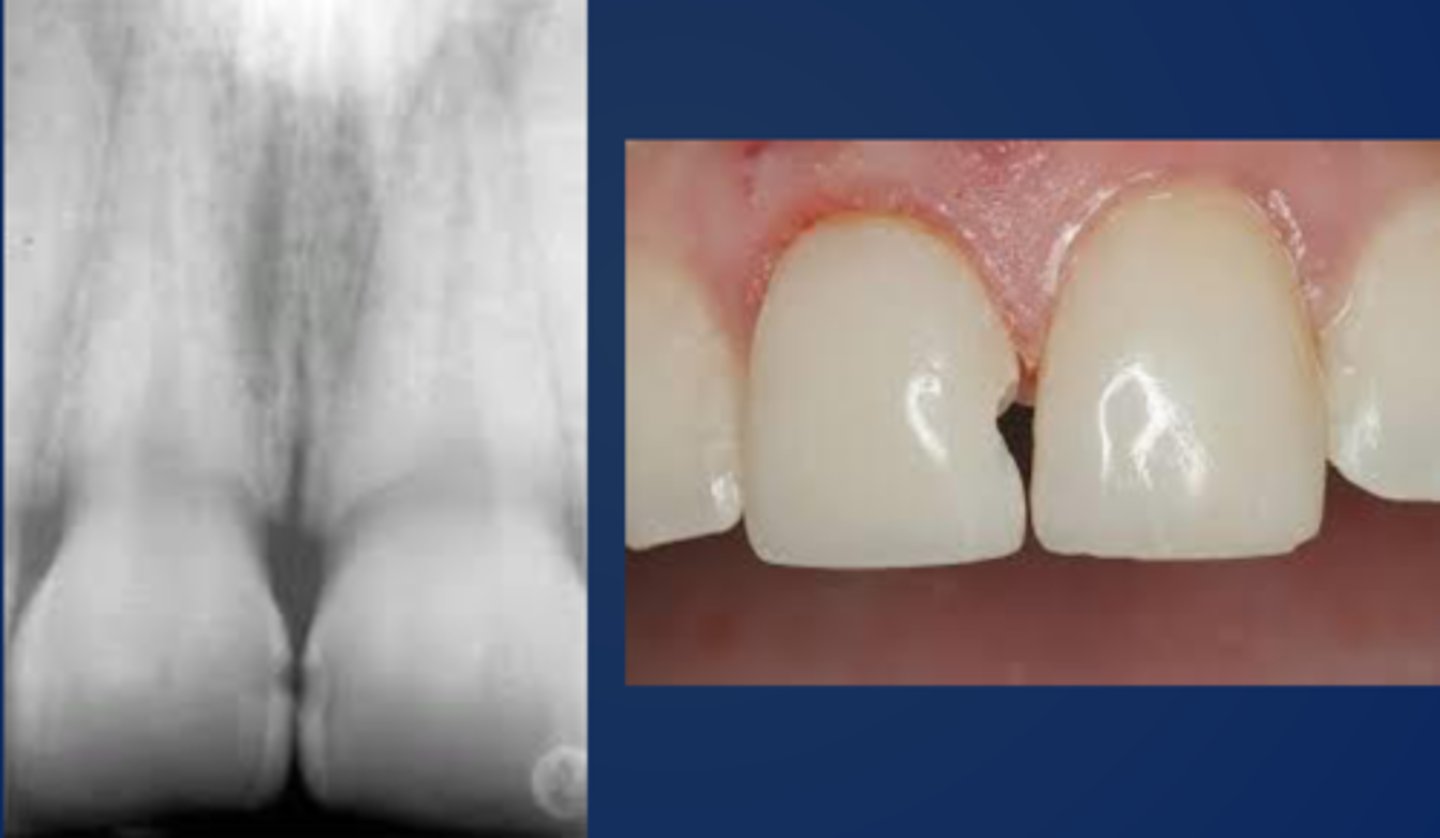

Class III cavity prep and restoration is a procedure that involves what?

the proximal surface of anterior teeth without incisal edge

Where is most of the lesion for Class IIIs?

lesion is cervical to the contact area

What causes lesions to be within the cervical to the contact area?

due to inconsistent/no flossing